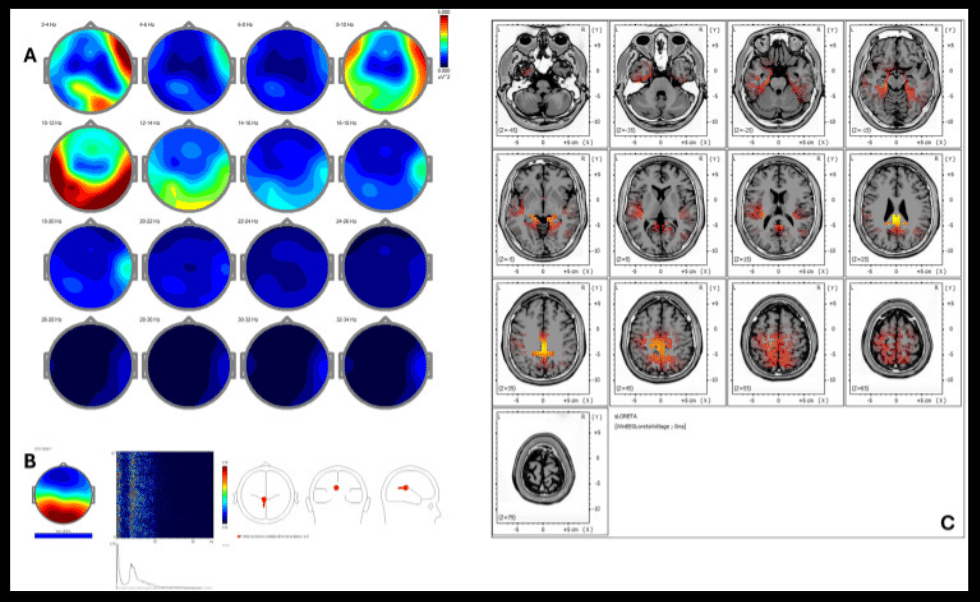

El estudio, de carácter retrospectivo, incluyó a cinco personas con exposición prolongada a estrés laboral. A través de 18 sesiones de REAC BWO-G, se evaluó la actividad cortical antes y después del tratamiento mediante técnicas avanzadas de análisis neurofisiológico (qEEG, ICA y sLORETA).

- Tendencias consistentes hacia una mayor simetría en bandas clave del EEG (delta, theta y alfa).

- Reorganización de la actividad cortical hacia redes asociadas con regulación emocional y cognición.

- Mejoras clínicas percibidas en estabilidad emocional, calidad del sueño y claridad mental.

- Patrones neurofisiológicos compatibles con una mayor resiliencia frente al estrés.

Los autores subrayan que estos hallazgos están en línea con la literatura científica que vincula el estrés crónico con alteraciones de conectividad cerebral. Aunque se reconoce la necesidad de estudios más amplios y controlados, los resultados sugieren que intervenciones no invasivas como REAC BWO-G podrían apoyar la recuperación funcional en contextos de estrés severo, sin efectos adversos reportados.